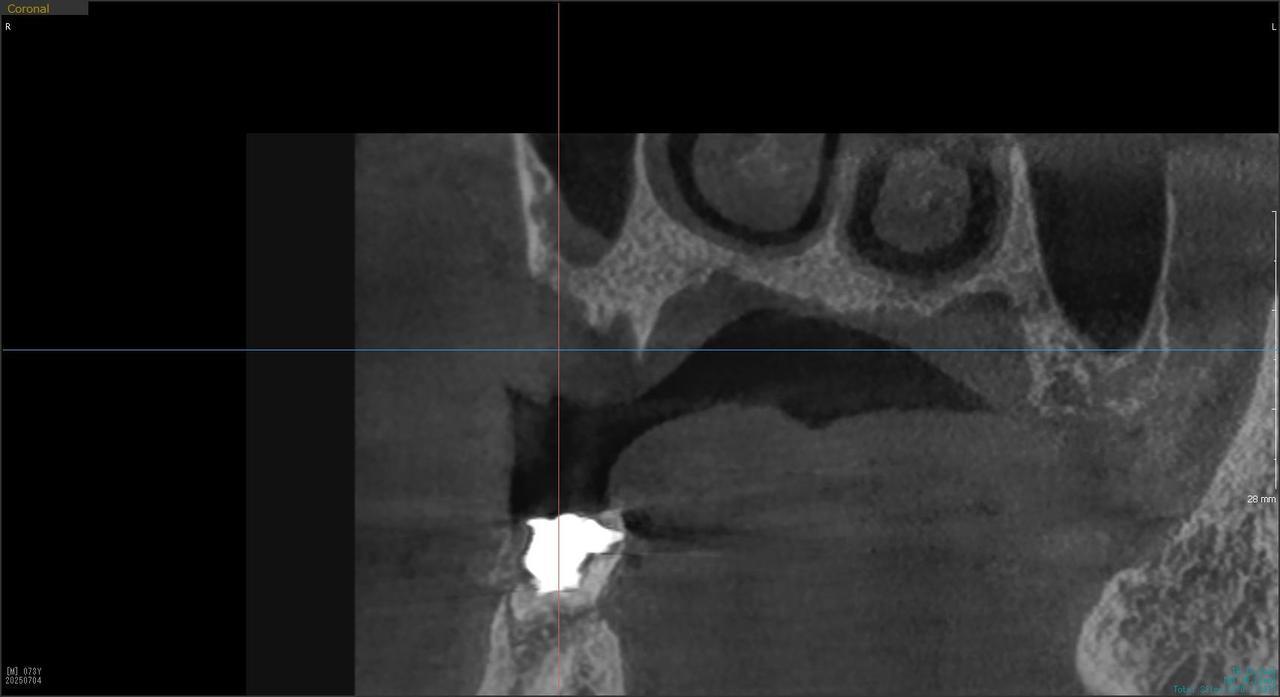

5.左上4番のインプラント抜歯即時埋入、左上6番の上顎既存骨1から2mmのグラフトレスサイナスリフト、左下56の大幅な骨欠損により、下顎神経の損傷を回避するために、ショートインプラントを使用し、左下56にインプラントを埋入し、最終補綴物は、左上456の3ユニットのジルコニアブリッジし、左下56は、ジルコニアの連結冠を装着したケース

Before

枚方市のインプラントの症例

M・I 様 女性 70代

症状としては、左下56は、歯周病で欠損したと考えられるが、かなりの骨欠損をともなっていた。左上456に関しては、動揺が大きく、炎症が起き、排膿、および、歯性上顎洞炎を起こしていた。

治療法としては、動揺がひどくなってきて、炎症の症状もあったため、左上56の抜歯を希望。インプラント治療をその後、希望したため、左上4に関しては抜歯即時埋入。左上6に関しては、既存骨1から2mmでインプラント治療が厳しい状態であったが、グラフトレスサイナスリフトを行い、治療期間5か月はかかるということを説明して、インプラント埋入をおこないました。その後、2か月半後、大幅に骨が欠損している下顎56に対して、ショートインプラントを使用して、下顎神経の損傷を避けて、インプラント埋入を終えています。その後2か月後に光学印象で印象を行い、上顎刺億456歯、3ユニットのジルコニアブリッジを装着。下顎左側56に関しては、骨欠損が大きいため、歯冠長がだいぶ長くなるため、ジルコニアの連結冠を装着して治療を終えた。

治療結果は、上顎6に関しては、既存骨が少なく、厳しい治療ではありましたが、5か月で治療を終え、患者様の負担を最小限に抑えるができたと考えます。(従来のサイナスリフトでは、このようなケースでは1年以上、1年程度の治療期間がかかるか、治療が不可能と言われるケースだと考えます。)また、下顎は骨欠損が大きく、下歯槽管のリスクが起きることが考えられますが、ショートインプラントを使用することで安全に治療を行うことができました。

治療の期間・回数:治療期間5か月(上顎456 3ピースブリッジの治療は5か月(上顎既存骨が2mm程度しかなく、骨結合に時間がかかるケースであったために、5か月の治療期間が必要であった。)(左下56に関しては2か月半で治療を終えています。)治療回数は、13回。

治療の価格:1,474,000円(税込)

治療費の内訳:左上46および左下56のインプラント基本料(フィックスチャー及び手術費用、投薬費用、レントゲン費用、インプラント上部費用(アバットメントおよびジルコニアクラウンの費用用)330000円(税込み)×4本分 1320000円(税込)。左上5ジルコニアポンテック費用88000円(税込)。オプション費用、左上4抜歯即時埋入加算(人工骨費用を含む)+グラフトレスサイナスリフト費用 33000円(税込)、左上6グラフトレスサイナスリフト費用 33000円(税込)

治療のリスクや副作用:手術後に、痛みや腫れ、出血、合併症などを引き起こす可能性があります。噛む感覚がご自身の歯と異なる場合があります。見た目がご自身の歯と異なる場合があります。手術後にメインテナンスを継続しないと、インプラントが抜け落ちる可能性があります。